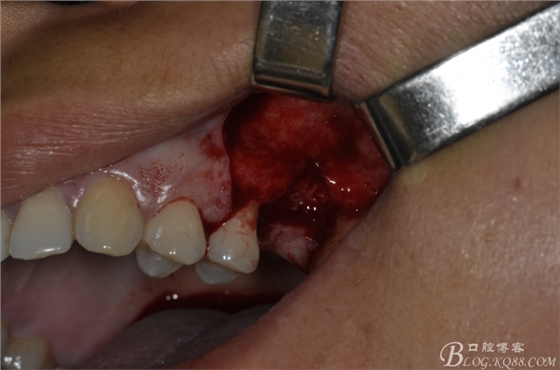

術(shù)中照片。

超聲骨刀切開骨外板 上頜竇外提一例